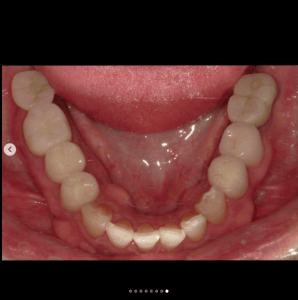

銀歯の中にできた虫歯の症例です。

「痛くないから今は虫歯がない」と話す方がいらっしゃいますが、それは大きな間違いです。

大人になってからの虫歯は痛みが出ることの方が圧倒的に少なく、口の中の病気は基本的に自覚症状と病気の重さが比例しません。

全ての銀歯の中に虫歯があるわけではありませんが、以下の理由から虫歯には注意が必要です。

1.銀歯はかけたり割れたりすることは絶対にないが、力がかかると”たわむ”

→ゆえに汚れが隙間に入りやすい

2.接着剤がつきやすいので、取れずらい

→ゆえに汚れもつきやすい

この症例のように、自覚症状が無くても銀歯を外してみたら大きな虫歯があるというケースも少なくありません。

しっかり検査、診断してくれるクリニックに定期的に行くことをおすすめいたします。